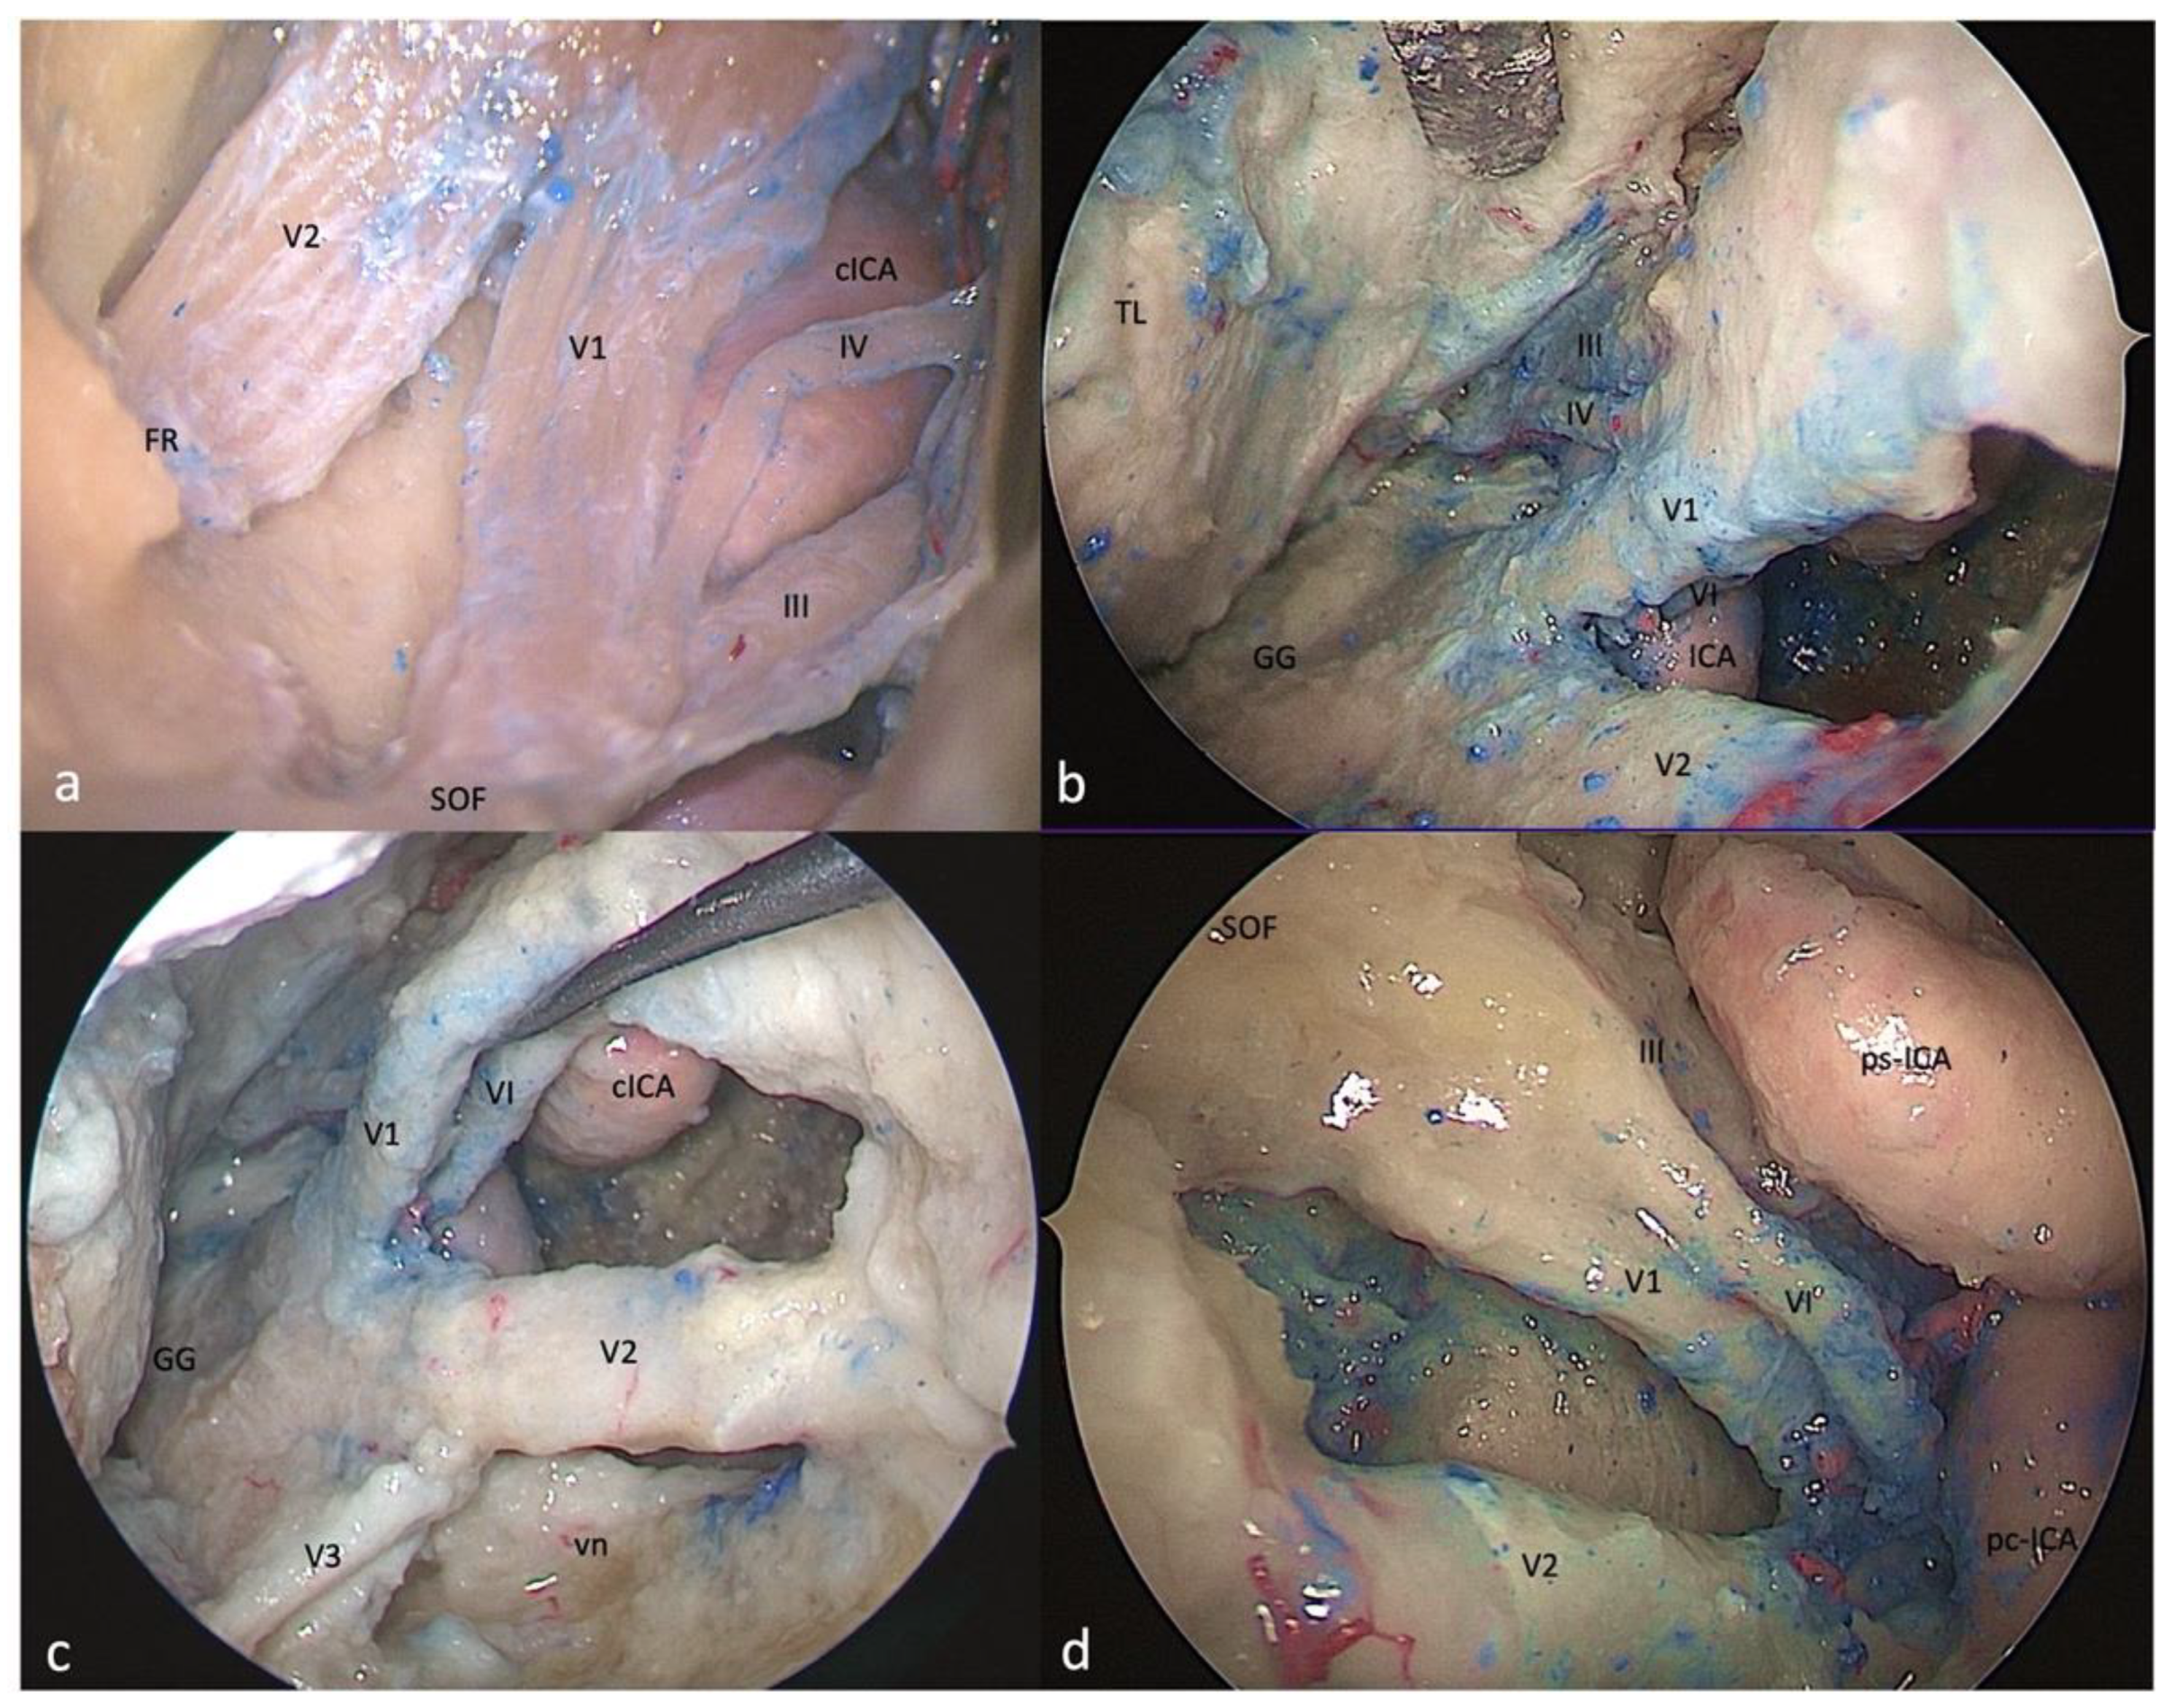

3.3. Supratrochlear Triangle (Paramedian)

3.3.1. FTOZ Perspective

3.3.2. SETOA Perspective

3.3.3. EEEA Perspective

3.4. Infratrochlear Triangle (Parkinson’s triangle)

3.4.1. FTOZ Perspective

3.4.2. SETOA Perspective

3.4.3. EEEA Perspective